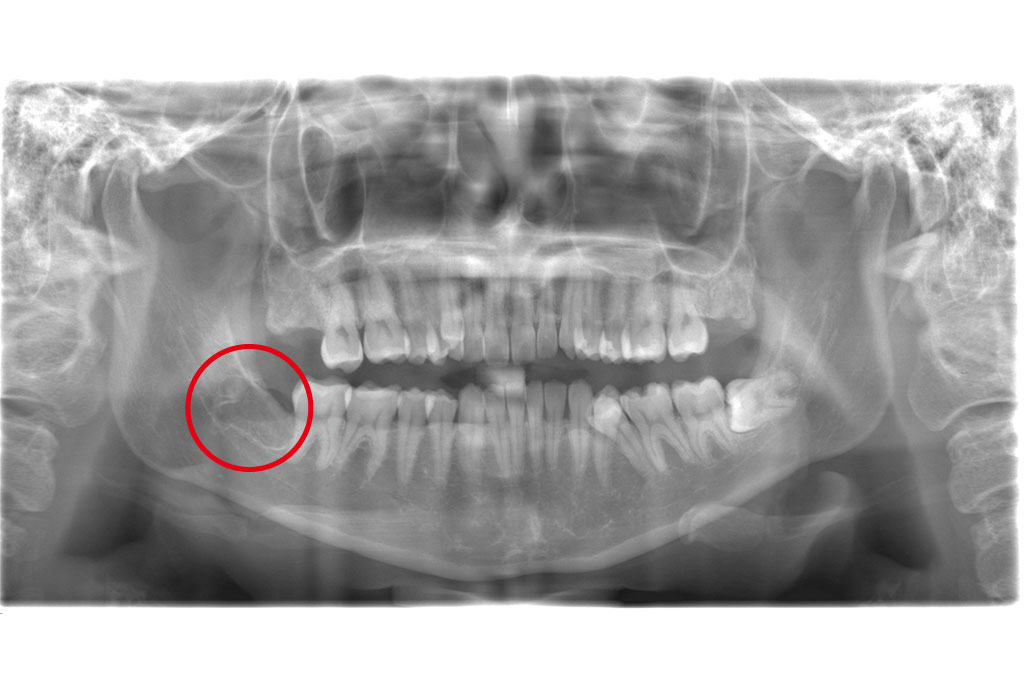

Tさまの歯を審査診断してみると、左上のブリッジのところや右上の奥歯、左下の治療していない歯や根の治療されている歯に亀裂が入っていたため抜歯という判断をさせていただきました。

まずは一番気になっていた左側上下からスタート。

その後左上をスタートし、完成しました。

根の治療をしている場所は、噛む力が強い方などは注意が必要だと改めて実感したケースです。